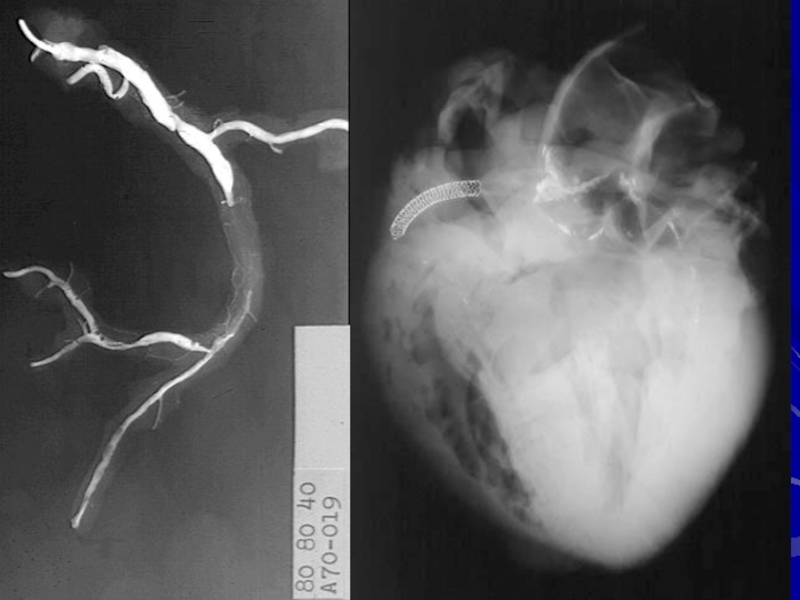

Слайд 7Норма

Острый коронарный синдром

Стабильная неосложненная бляшка

Нестабильная осложненная бляшка (интракоронарный тромбоз)

Стабильная хронически

-окклюзирующая бляшка

Неполная острая окклюзия

Полная острая окклюзия

Нестабильная стенокардия

ОИМ “ST–”

ОИМ “ST ↑”

Topol

E.J., J. Am. Coll. Cardiol., 2003, 41, suppl. S, 123S-129S.

АТЕРОТРОМБОЗ – ВЕДУЩИЙ ФАКТОР РАЗВИТИЯ ОКС И ПРОГРЕССИРОВАНИЯ ХРОНИЧЕСКОЙ ИБС